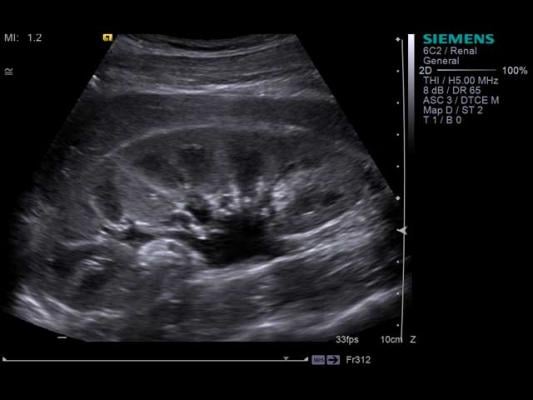

November 30, 2018 — VigiLanz and Cincinnati Children’s Hospital Medical Center recently announced a collaboration that leverages Cincinnati Children’s research on pediatric nephrotoxic kidney injury and VigiLanz’s capabilities to commercialize a solution for acute kidney injury (AKI) in pediatric patients. Dubbed NINJA, or Nephrotoxic Injury Negated by Just-in-time Action, the solution enables real-time identification and monitoring of patients at risk for AKI due to exposure to nephrotoxic drugs.

Leveraging NINJA algorithms built into VigiLanz rules, an AKI monitoring dashboard lists all patients that meet the NINJA exposure criteria as well as the criteria that put the patient in the at-risk category. These criteria include medication exposure, serum creatinine data and patient history of AKI. When patients meet at-risk criteria, they are placed on the monitoring list in real time, where they remain until 48 hours after their risk has passed.